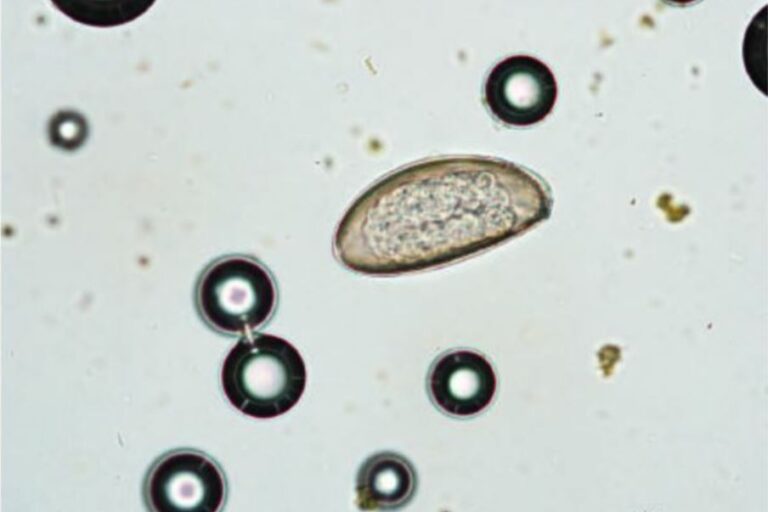

Intestinal parasites in rabbits and guinea pigs

Dental disease and inappropriate feeding are common causes of diarrhoea. Parasites, in contrast, play a…